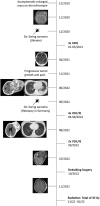

Background: Ewing sarcoma is a rare malignant neoplasm that is primarily localized in bone tissues. The prognosis for patients with a newly diagnosed localized Ewing sarcoma has been greatly improved by multimodality treatment. However, treating patients with disseminated or recurrent disease is challenging, with a 5-year overall survival rate of <30%. Case Report: A 17-year-old female with an asymptomatic tumor of the left temple underwent 3 cycles of vincristine, ifosfamide, doxorubicin, and etoposide and achieved partial remission. However, the patient refused further chemotherapy and surgical intervention and was lost to follow-up. After 7 months, the patient presented again with a sizeable tumor on her left temple and worsening symptoms. Chemotherapy with alternating cycles of vincristine, doxorubicin, cyclophosphamide, ifosfamide, and etoposide according to the EURO EWING 2012 trial was initiated. After a positive response, debulking surgery was performed, followed by postsurgical radiation, and partial remission was achieved. Conclusion: Optimal treatment protocols for recurrent Ewing sarcoma are lacking. Treatments are individualized based on the patient's response to treatment and the decisions of tumor boards. Patients with rare tumors such as Ewing sarcoma benefit from multidisciplinary collaboration, resulting in improved quality of care and treatment outcomes.